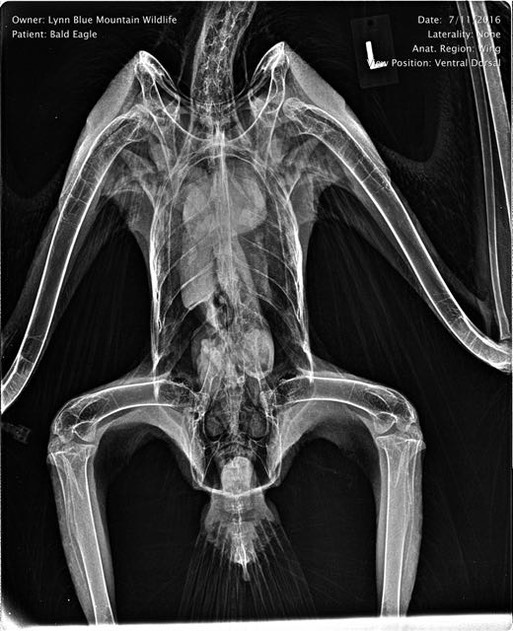

An exam revealed the eagle was extremely emaciated and dehydrated, but had no obvious injuries. A radiograph showed a slight abnormality in the right shoulder. Fortunately she is responding well to supportive care and will hopefully make a full recovery. Below she is recovering from anesthesia.